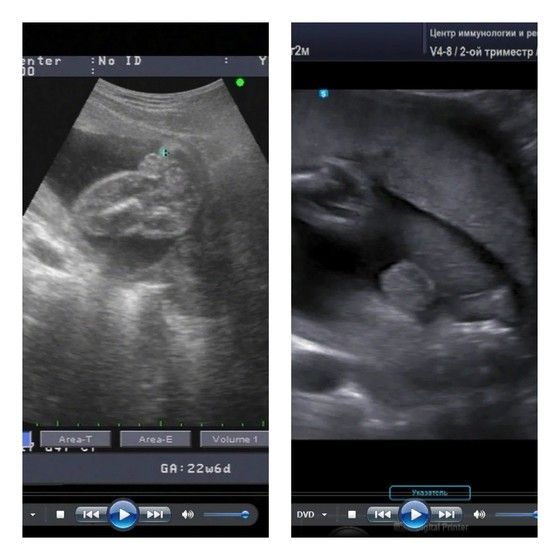

Пол малышаДевочки у кого дочки если остались у вас фотки с узи где видно пирожок можете покидать?Вот моё фото

Наш пирожок 16 недель🥰🥰🥰

Вот в 19 недель

20 недель, девченка

Вот моя девочка ♥️